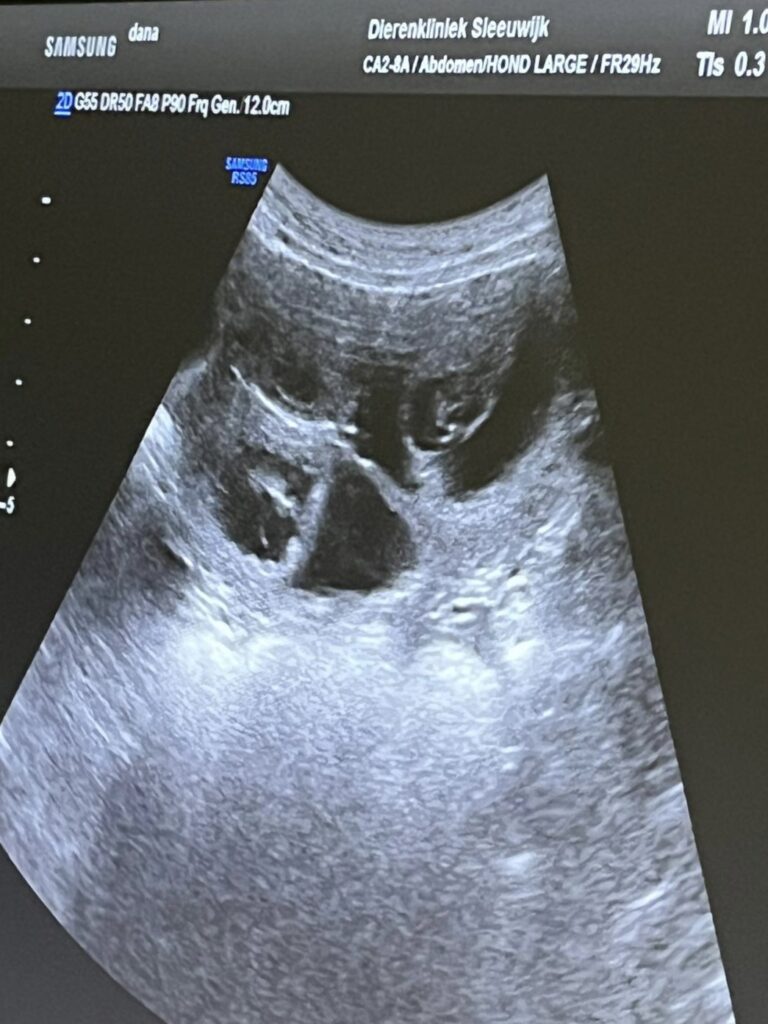

Vandaag was dan eindelijk de echo om te zien of Mildred daadwerkelijk drachtig is en al meteen zagen we pupjes in beeld verschijnen!! Fantastisch!! Ik was er niet helemaal zeker van, zij was de vorige keer de hele dracht ziek, nu heeft ze nergens last van. At ze de vorige keer nagenoeg niets, nu heeft ze voortdurend zin in met name lekkere dingen….. zag wel dat de tepels dikker werden en voelde ook al een buikje…..maar ja, zij gaat meestal na de loopsheid de schijndracht in en dan hebben ze dat ook. Helemaal blij dus dat ze drachtig is en er een flink aantal pupjes voorbij kwamen. Dat hebben Gahan en Mildred super gedaan!! 🥰 Er wordt erg naar de pupjes uitgekeken, ook in Noorwegen is de blijdschap groot ❣